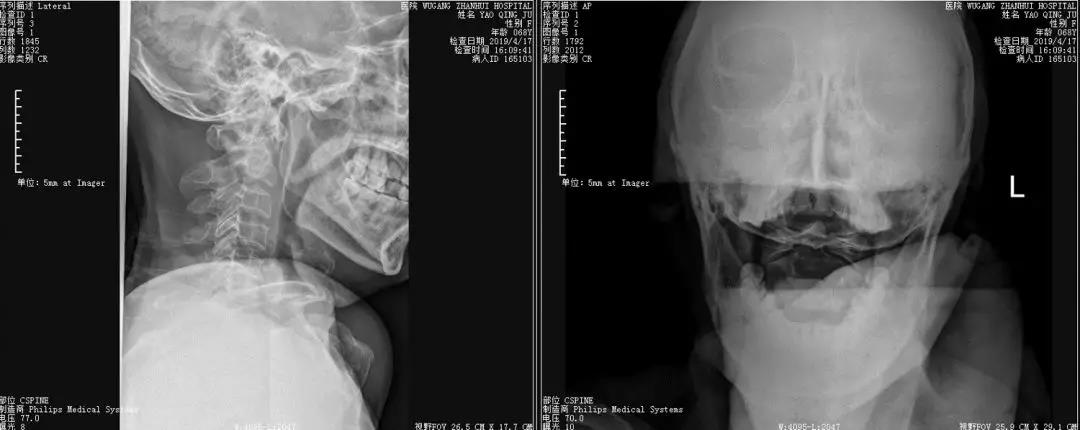

骨卫士特聘专家、原解放军307医院范海涛主任在会上分享了一例C2枢椎齿状突骨折并颈髓挫伤患者病例 。患者为67岁女性,因摔伤致四肢麻木,不能活动。

患者影像资料如下:

▲术前侧位及张口位